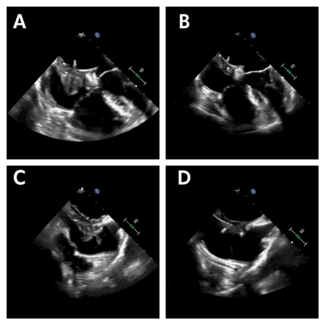

Muhammad Moolla, MD; Hatem Linjawi, MBBS; Dylan Taylor, MD; Anoop Mathew, MBBS

Muhammad Moolla, MD; Hatem Linjawi, M...

The author report a case of device-related thrombus complicating transcatheter atrial septal defect (ASD) device closure using the GORE Cardioform ASD Occluder, which consists of a thromboresistant-expanded polytetrafluoroethylene material...

The author report a case of...